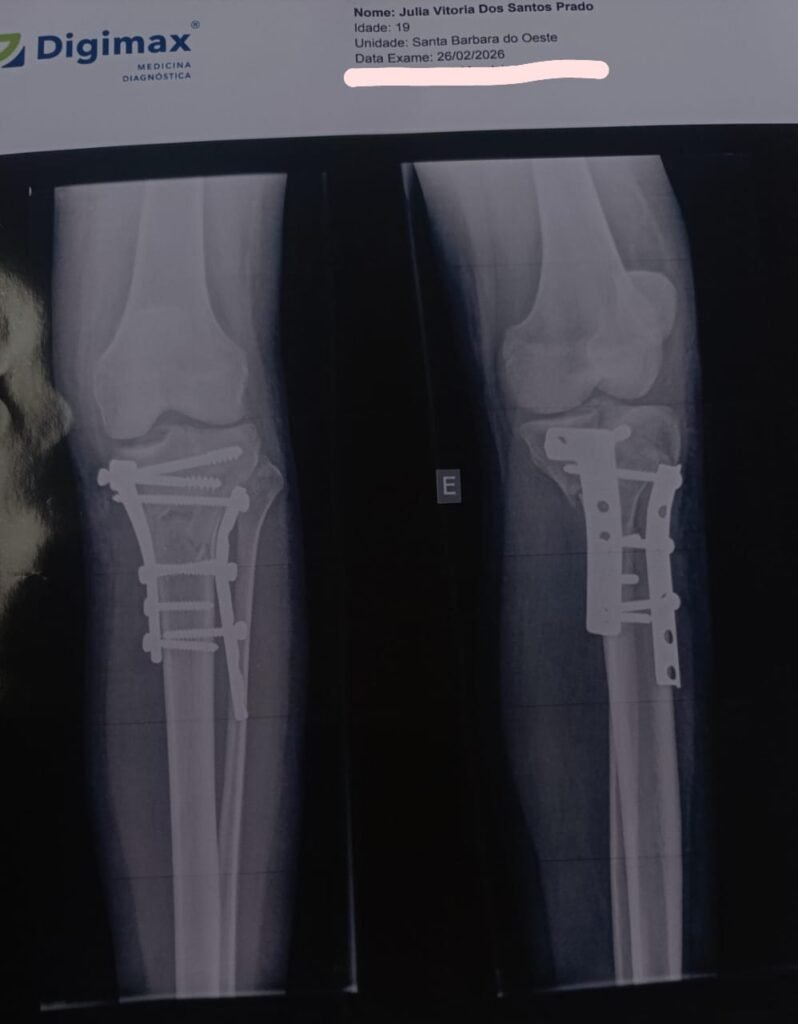

Durante a consulta médica, novos exames de raio-X foram realizados e os médicos constataram que seria necessária uma cirurgia para tratar as fraturas na tíbia e na fíbula. O procedimento foi realizado no dia 4 de fevereiro, no Hospital Santa Bárbara.

Após a cirurgia, Júlia iniciou o período de recuperação e aguardava o retorno médico. Em uma nova consulta, atendida por outro ortopedista, ela acabou sendo liberada para iniciar sessões de fisioterapia. No entanto, ao mostrar posteriormente a imagem do seu raio-X para um colega ortopedista, surgiu a suspeita de que algo poderia estar errado com o resultado do procedimento.

Diante da dúvida, Júlia buscou uma avaliação mais especializada com um ortopedista especialista em joelho. Durante essa consulta, o médico identificou problemas no resultado da cirurgia, entre eles placas e parafusos soltos, além da utilização de um tipo de placa considerado inadequado para o tipo de fratura que ela sofreu.

Segundo o especialista, a situação exige uma cirurgia corretiva com urgência, já que o tempo desde a primeira intervenção já se aproxima de um mês. Caso o osso consolide de maneira incorreta, há risco de complicações graves no futuro, como dores constantes, dificuldade de mobilidade e até impossibilidade de voltar a andar normalmente.